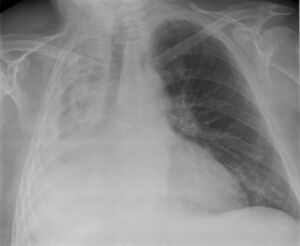

التشخيص

همود الرئة في الفص الأيمن السفلي كما يظهر بالأشعة السينية على الصدر.

• الأشعة السينية للصدر (الانخماص ما بعد العمليات الجراحية يظهر في الجزء الأدنى من الرئتين)

• التصوير المقطعي

• منظار الشعب الهوائية